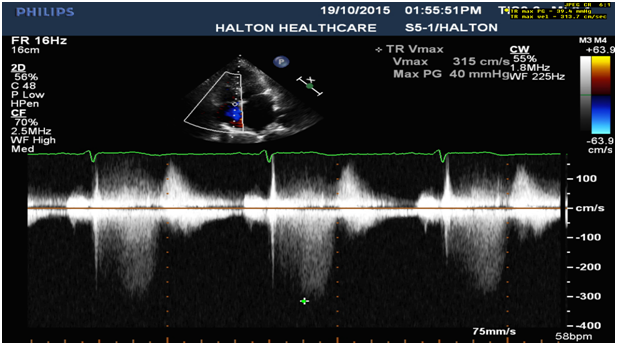

7. Mild pulmonary hypertension (Figure 7).

Figure 1: Severe MVP with Partial Flail Posterior Leaflet presented by parasternal LAX view with TTE (Left) and sagittal view at 91○ with TEE (P2 segment) (Right).

Figure 7: Tricuspid regurgitation: Mildly increased right ventricular systolic pressure, 43 mmHg.